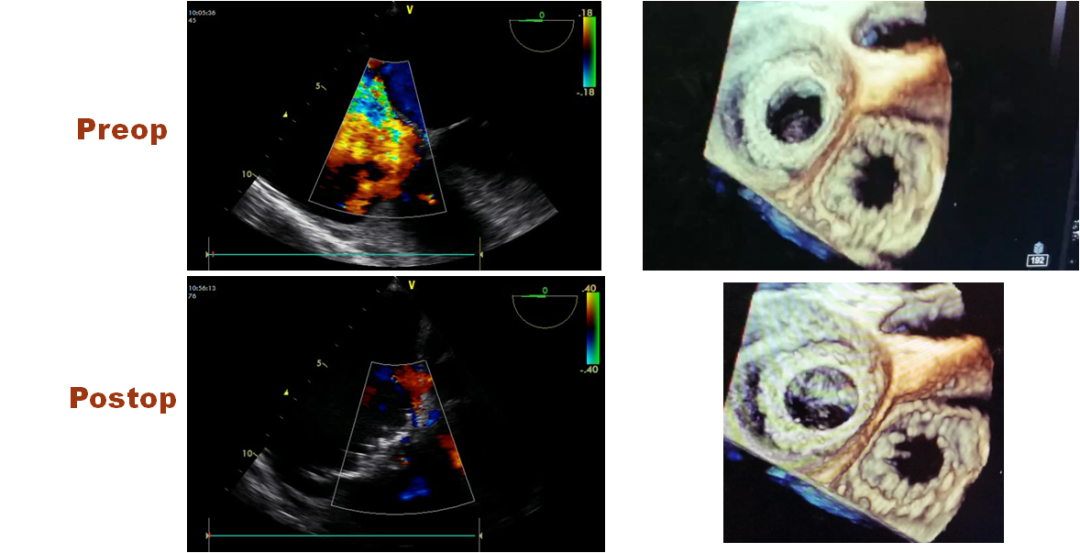

Right Atrial Access

图片

Transesophageal echocardiography

STS risk             9.2± 5.2%

EuroScoreII        7.4 ± 4.8%

Threepts with cancer

SICK,  WEAK  &  RISK!     (3 K)

生物标志物高敏肌钙蛋白

Theinitial clinical results  is satisfactory and promising